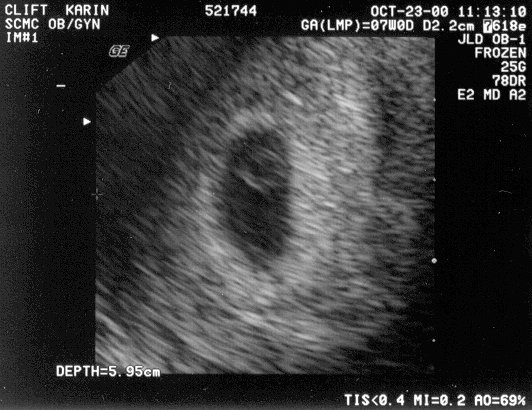

October 23 Saw the heart beating on ultrasound #1, #2